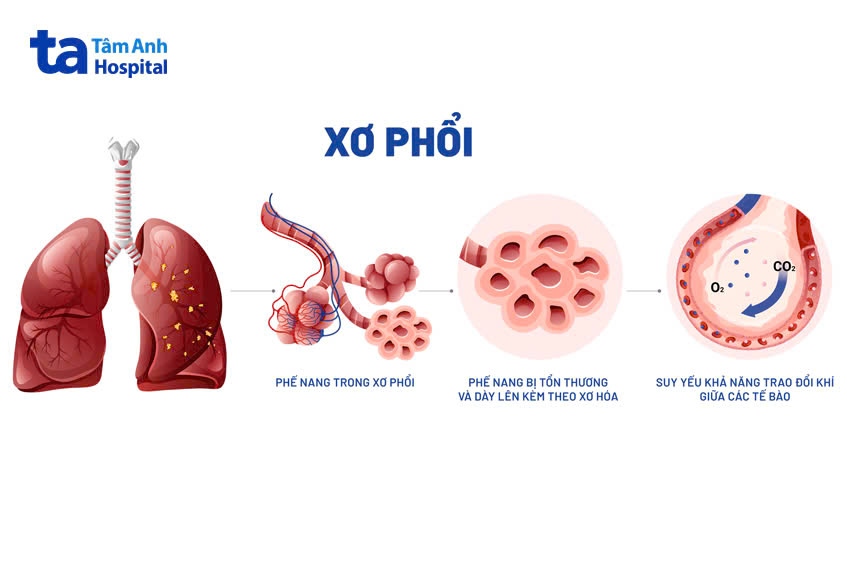

Xơ phổi là một nhóm các bệnh phổi nghiêm trọng ảnh hưởng đến hệ hô hấp. Xơ phổi gây sẹo và làm dày mô phổi. Nó ảnh hưởng đến mô liên kết trong phổi và phế nang (túi nhỏ tận cùng chứa khí của phổi). Tổn thương phổi dần trở nên tồi tệ hơn theo thời gian. Các mô phổi cứng, không giãn nở tốt như bình thường, khiến việc thở trở nên khó khăn hơn. Xơ phổi có thể gây khó thở ngay cả khi bạn thực hiện các công việc sinh hoạt thường ngày. (1)